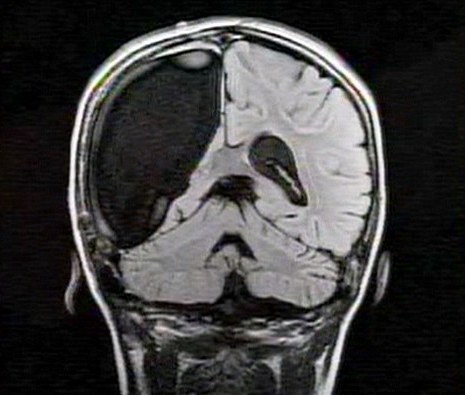

中新網(wǎng)3月26日電 據(jù)英國媒體26日報道,一名9歲的英國女孩在經(jīng)歷了右腦切除手術(shù)后奇跡康復(fù),令醫(yī)生和家人無比震驚。

報道稱,現(xiàn)年9歲的卡梅倫•莫特在手術(shù)中切除了她整個右半邊的大腦,而在經(jīng)歷如此重大的手術(shù)后能迅速康復(fù),莫特的奇跡也讓醫(yī)生和她的家人驚嘆不已。年幼的莫特也沒有因?yàn)椴“Y而放棄對夢想的追求。

卡梅倫莫特在3歲那年患上一種被稱作大腦功能紊亂“拉斯穆森”綜合癥,這種病癥誘發(fā)患者的無序暴力行為和嚴(yán)重的癲癇。醫(yī)生建議,治療這種病癥只能通過嘗試消除引發(fā)此癥狀的大腦組織。而手術(shù)讓莫特失去了幾乎整個半邊的大腦。

據(jù)悉,莫特在手術(shù)后已經(jīng)可以跑動和玩耍,她在術(shù)后的第四周離開了醫(yī)院。醫(yī)生表示,雖然右半邊大腦的切除可能會給莫特帶來半身不遂的風(fēng)險,但孩子剩余的大腦仍具有很強(qiáng)的重組和布線能力。